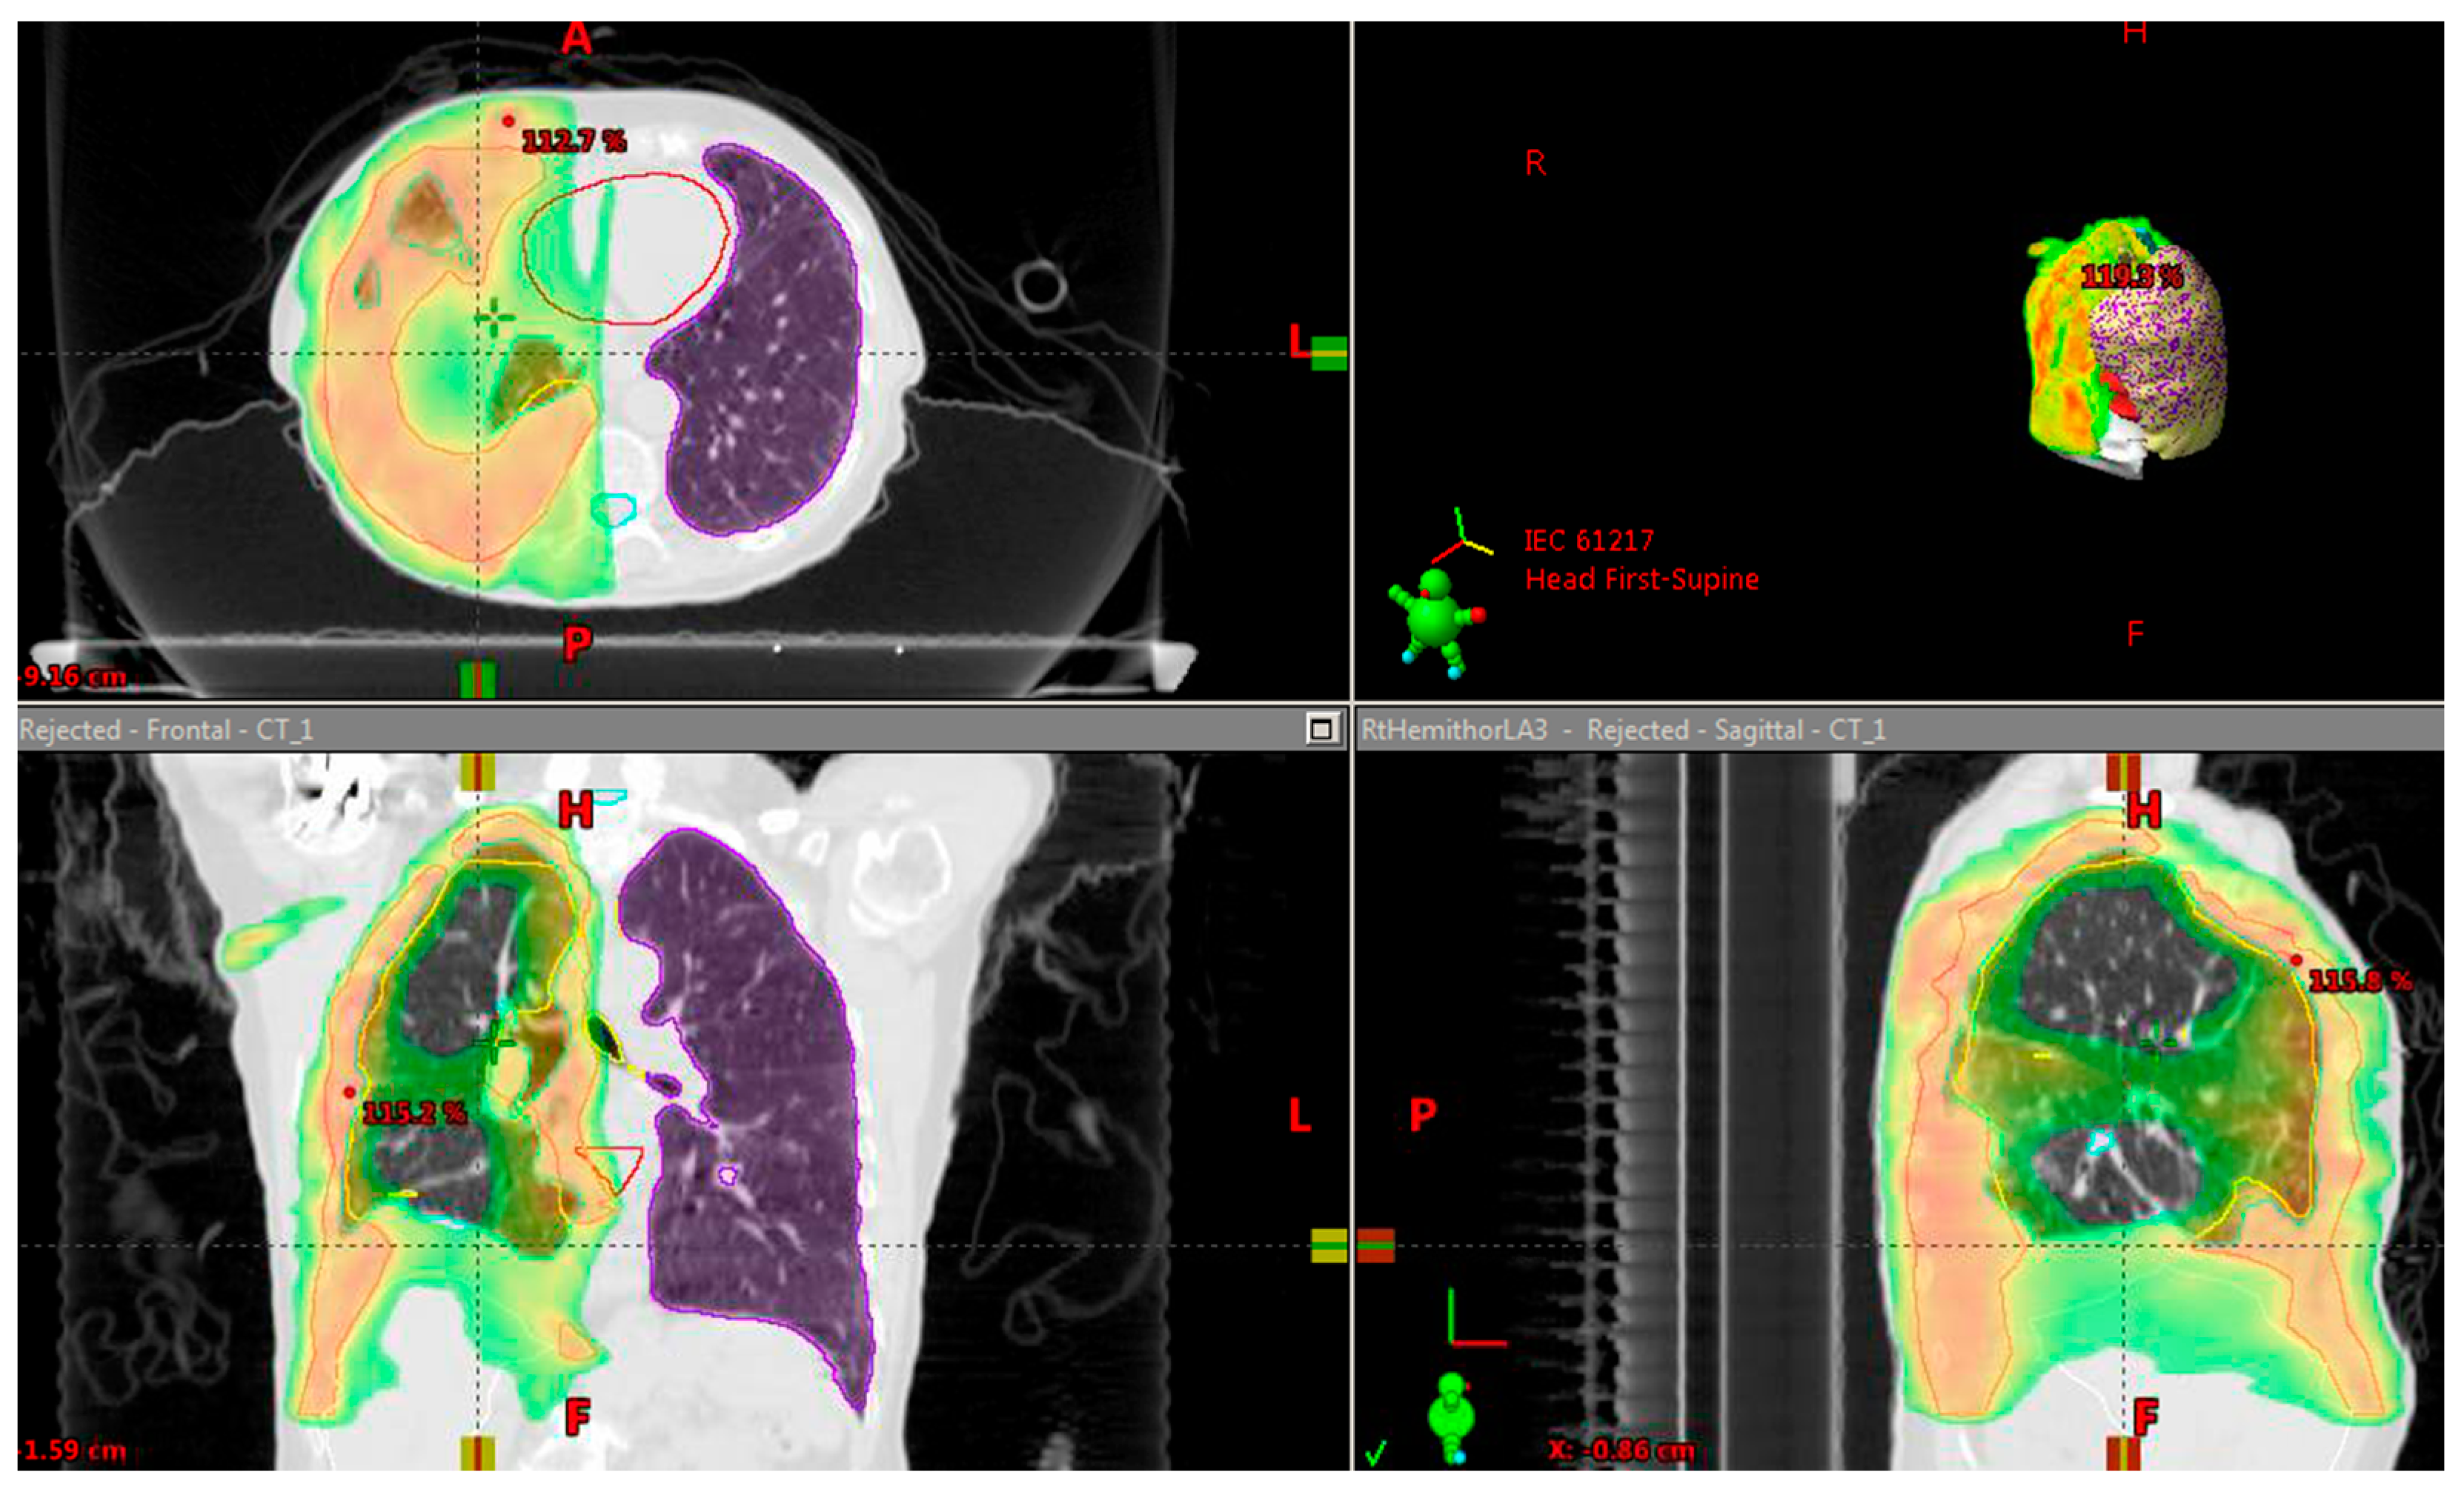

3. Results

3.1.1. Patient 1

3.1.2. Patient 2

3.1.3. Patient 3